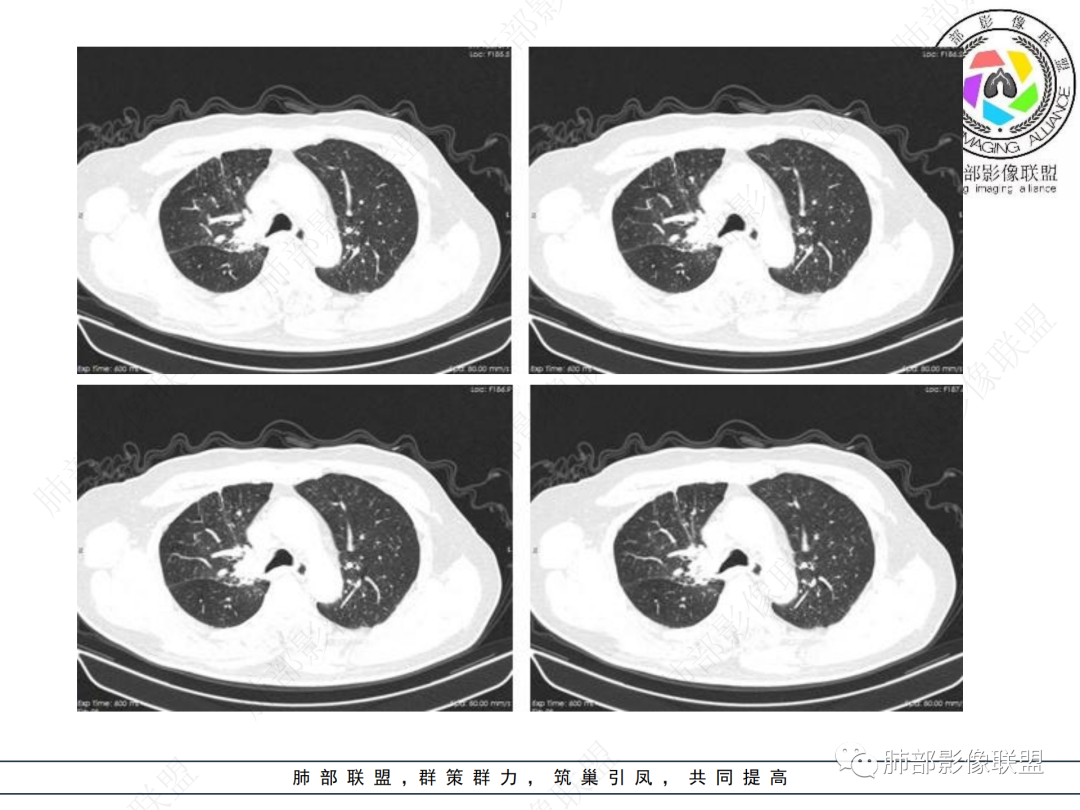

右肺上叶可见一团块影,边界清,有膨隆有凹陷,边缘可见毛刺,斜裂可见牵拉,不均匀强化,内可见液化,临近支气管未见明确阻塞,考虑腺癌可能,鉴别脓肿,结核等

右肺上叶团块,边缘毛糙,长索条,周围斑点影,邻近胸膜增厚,不均匀强化,其内小低密度灶边界清,考虑炎性肉芽肿,腺癌待排

右上胸廓缩小,叶间裂移位,尖段软组织影,前段支气管壁增厚,双上肺多发结节及条片影,增强后尖段软组织影内见多发低密度影,呈环状强化,考虑慢性肉芽肿,腺癌待排

男性,69岁 反复咳嗽2年余,加重3天入院。CT示右肺上叶尖段不规则实变影,周边伴条索影,支气管未见明显堵塞,增强不均匀强化,考虑为恶性,腺癌可能

老年男性,慢性病程,右肺上叶团块影,边界清晰,边缘毛刺,脐凹征,胸膜牵拉,不均匀强化,支气管壁增厚,考虑恶性,腺癌可能,鉴别肉芽肿、结核

男,69,反复咳嗽2年,加重3天入院,右肺上叶软组织密度肿块影,边界尚清晰,边缘见毛刺及胸膜牵拉,右肺上叶支气管壁增厚,增强扫描不均匀性强化,考虑腺癌可能,鉴别炎性病变。

老年男性,右肺上叶体积小,见高密度团块,边缘模糊,并见多发长索条,增强后不均匀强化,考虑炎性肉芽肿性病变,鉴别腺癌

病程长,右肺上叶团片影,边缘毛糙,部分膨隆,长索条,周围长条索及结节,邻近胸膜增厚,不均匀强化,首先考虑炎性肉芽肿,鉴别腺癌

右肺上叶团块周围多发斑索,不均匀强化,支气管无明显堵塞,咳嗽两年,首先考虑慢性炎性病变,肺结核可能,鉴别腺癌

右肺上叶见不规则团块,边缘清晰,周围可见长索条及斑片影,胸膜顶增厚,右侧斜裂部分增厚,右上肺体积略缩小,增强后不均匀强化,考虑炎性肉芽肿性病变,结核?鉴别腺癌

右肺上叶体积变小,见不规则实性病灶,边缘有平直,长软毛刺,邻近胸膜明显增厚,叶间胸膜牵拉上提、局部凹陷;病灶周围不干净,可见长索条影;近端支气管壁略增厚。增强后增强不均匀,有低密度坏死,间隔较厚。考虑慢性炎性肉芽肿,结核可能,鉴别腺癌。

右侧胸廓变小,右肺上叶团块,边缘毛糙,长索条,周围斑点影,邻近胸膜增厚,气管不规整,密度不均,不均匀强化,考虑炎性肉芽肿,腺癌待排。

右肺上叶尖后段不规则斑块病灶,后缘以斜裂为界,有边缘平直,周围见纤维及多发小卫星灶,邻近胸膜反应性增厚,纵隔胸膜下少量积液,同时右肺中叶内侧段支气管扭曲及牵引性扩张,周边见爬行征,胸廊入口变窄,纵隔未见淋巴结肿大,综合上述慢性炎性肉芽肿,结核可能性大,支气管镜肺泡灌洗!

内部支气管近端狭窄,远端粘液栓

结核要考虑下

内部血管也通畅

边缘也算平直

不踏实的是这里稍膨隆

结合本病例,老年男性患者,慢性病程,急性加重,无吸烟史,影像学表现为右肺上叶尖后段斑片实变密度影,整体边界清晰,边缘平直收缩为主,周边散在纤维条索影,内部见支气管内粘液栓,血管影走形正常,没有明显破坏,增强扫描明显强化,缺乏典型分叶毛刺、胸膜改变,病灶也未显示清楚的磨玻璃勾边,病灶大而肺门纵隔未见肿大淋巴结,综合考虑慢性炎性肉芽肿可能性大。但恶性,结核能完全排除吗?我想对临床医生来说还是有很大考验的。